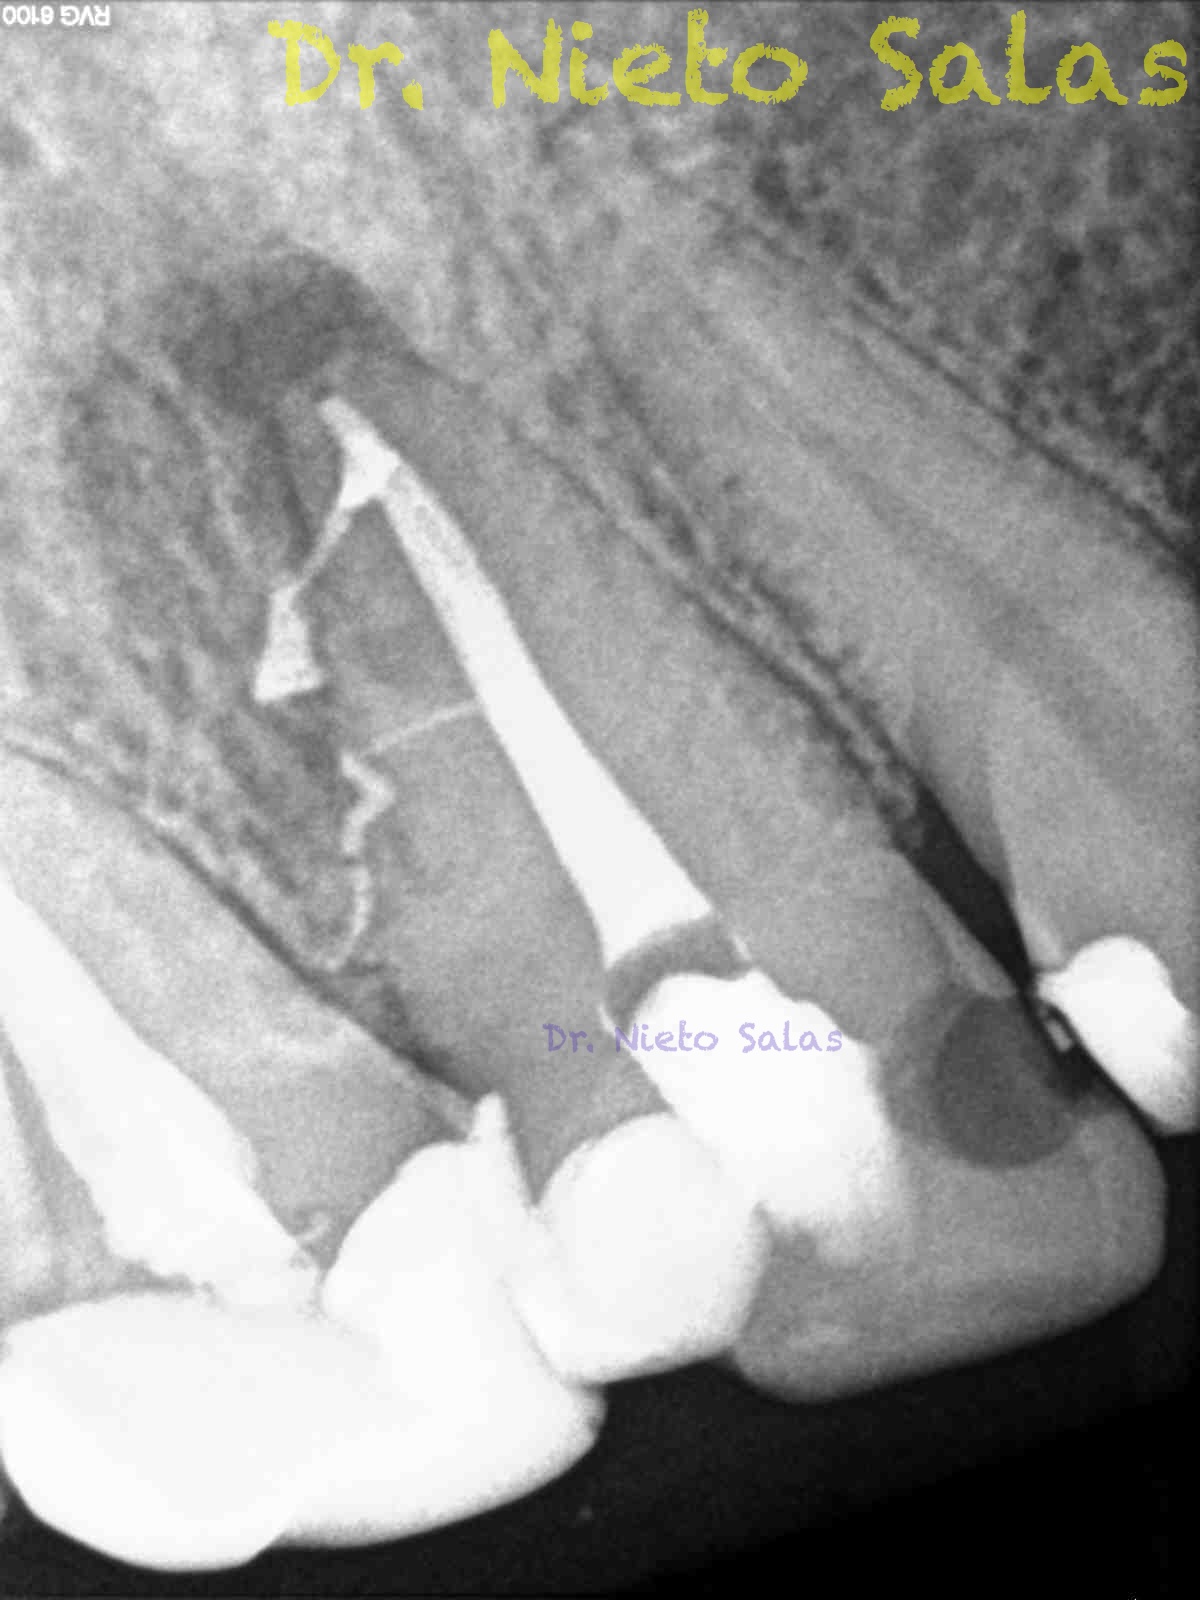

Y este sería el otro caso:

Es muy importante cambiar la proyección de las Rx para tener más información de como hemos sellado el sistema de conductos.

Como sabrás, son muchas las piezas dentarias que presentan conductos laterales, lo primero, es descartar que la imagen pueda ser una fractura vertical, después conformo el sistema de conductos, y si sospecho de un conducto lateral ( INTUICIÓN ) precurvo una lima de pequeño diámetro y exploro las paredes en la zona de puede estar. En ocasiones, puedes ver un pequeño puntito, la entrada, con el microscopio. (es raro).